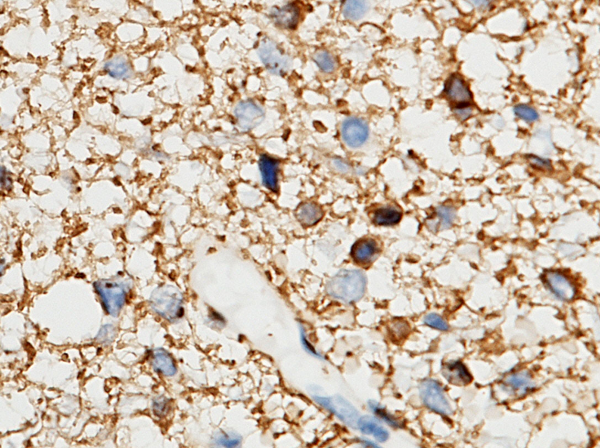

(Immunochemical staining of human GFAP in human clear cell tumors (brain) with rabbit polyclonal antibody (1:1000, formalin-fixed paraffin embedded sections).)

IHC (Immunohistochemistry)

(Immunochemical staining of human GFAP in human glioma with rabbit polyclonal antibody (1:1000, formalin-fixed paraffin embedded sections).)